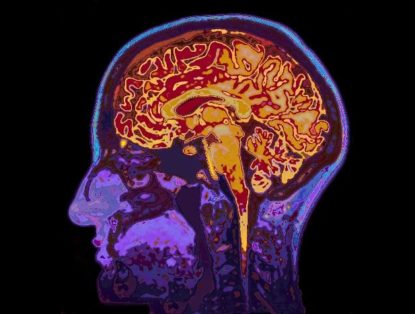

MRI brain scans can detect many issues in the brain, such as cysts, tumors, bleeding, swelling, inflammatory conditions, and other abnormalities. ...